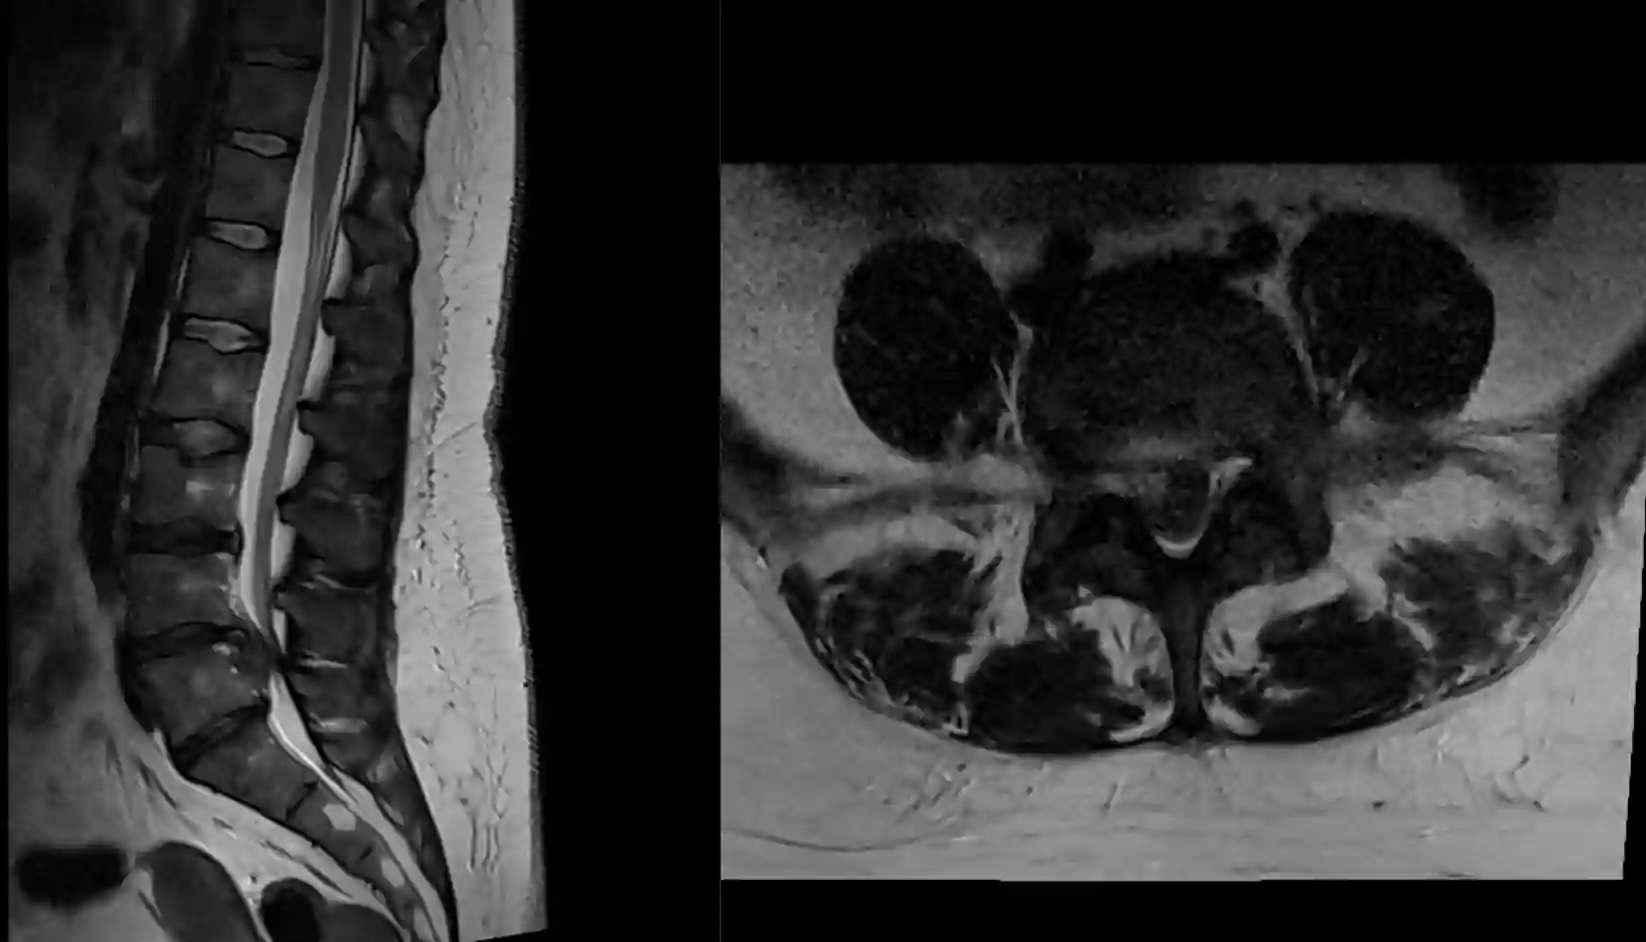

Der Goldstandard zur bildgebenden Beurteilung eines Cauda Equina Syndroms ist die MRT Bildgebung.

Sagittales und axiales T2 MRT Bild eines Patienten mit einem Cauda equina Syndrom auf Grund eines Bandscheibenvorfalls auf Höhe LWK4/5 mit folglicher Kompression der Cauda equina